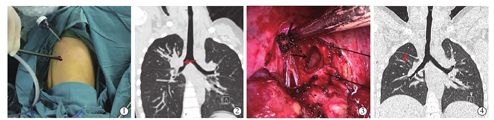

患儿取健侧90°卧位,腰部垫沙袋以增宽患侧肋间隙。手术采用单操作孔法:于患侧腋中线偏前第7肋间做长度约0.5~1.0 cm腔镜孔,放置5/10 mm Trocar,利用30°胸腔镜观察胸腔粘连情况及肺裂发育情况、病变位置,在腋前线与腋中线间第4肋间做2~3 cm操作孔(图1)。进入胸腔后轻柔牵拉和挤压肺,让患侧肺尽量萎陷。胸腔内有粘连者用电钩或超声刀分离粘连,暴露良好后,根据手术方案及术中情况,行楔形切除者准确定位后用卵圆钳固定病变组织,使用直线切割缝合器切下病变肺送病理检查,病变为良性者胸腔镜直视下行肋间神经阻滞。明确无活动性出血后温盐水冲洗胸腔,原腔镜孔放置胸腔引流管后关胸。行肺叶切除或肺段切除者切开病变肺叶韧带及胸膜,逐一游离出肺叶/段动、静脉及支气管。根据肺叶动、静脉粗细选择直线切割缝合器或Hemolock闭合并切断血管,使用Hemolock者近心端一般放置2个,以防Hemolock脱落导致出血。支气管一般选择直线切割缝合器切断,部分患儿近心端缝合1~2针加固残端,气管纤细者则直接切断后缝合,病肺切除后取物袋取出,常规行肋间神经阻滞、冲洗胸腔、放置引流管并关胸。

2例肿瘤位于右上肺支气管开口处患儿(图2)行袖式切除,打开纵隔胸膜,游离并切断肺动、静脉后,充分游离右上肺支气管及右主支气管,使得视野宽阔。组织剪剪除右肺上叶及部分右主支气管,保留右主支气管及中间支气管部分膜部(图3)。取物袋取出病肺,吸尽气管内出血及分泌物后间断缝合主支气管及中间支气管残端。缝合完毕后嘱麻醉师吸尽气管内分泌物及血液,鼓肺观察肺膨胀情况及有无漏气,确定吻合口良好、肺顺利膨胀后再次单肺通气。肺萎缩后常规行肋间神经阻滞、冲洗胸腔、放置引流管并关胸。

23例患儿中17例(73.91%)有不同程度胸腔粘连,2例因胸腔粘连辅助小切口下完成手术,其中1例肺囊肿合并感染的9月龄患儿,另1例为肺隔离症合并感染的5岁患儿。21例(92.30%)患儿在单操作孔下完成手术,所有手术包括肺叶切除17次、袖式切除2次、肺段切除1次和楔形切除4次。手术时间为(146.57±76.83)min,范围35~345 min;术中出血量为(42.39±45.12)ml,范围5~200 ml。术后引流管留置时间为(5.04±1.75)d,范围1~7 d;术后总引流量为(611.96±435.24)ml,范围50~1 500 ml;日引流量为(113.44±61.54)ml,范围18~215 ml;术后住院时间为(8.35±3.05)d,范围5~17 d。住院期间无死亡病例。出现肺部感染1例,经抗感染治疗后恢复。无肺不张、活动性出血、支气管胸膜瘘等术后并发症发生。术后病理检查提示:肺囊肿6例、肺隔离症4例、肺囊性腺瘤样畸形2例、硬化性血管瘤2例、机化性肺炎2例、支气管扩张2例、炎性肌纤维母细胞瘤1例、黏液表皮样癌1例、肺母细胞瘤1例、肺实变1例和结核性肉芽肿1例。近期随访中,所有患儿均恢复良好,复查胸部CT见患侧剩余肺叶代偿良好(图4)。

儿童患者血管、气管及肺组织均较细小,大龄儿童可使用成人器械,处理上与成人无异,对于低龄儿童,成人胸腔镜器械如直线切割缝合器并不适用[10,18]。对于该类患儿,处理血管时我们使用Hemolock夹闭,一般近心端使用2个Hemolock夹闭,远心端使用1个Hemolock夹闭,然后超声刀或组织剪切断血管,或直接用丝线结扎后切断血管。肺隔离症患儿的血管直接从主动脉发出,多数长期肺部感染,血管壁较脆弱,且多数合并有周围组织粘连,处理困难,一旦血管破裂出血量大,控制困难。我们的经验是,处理供血动脉时尽量稍远离主动脉,即便出现出血也有足够长的残端可以控制出血,保证手术安全。低龄儿童气管的处理则直接切断后用proline线连续或间断缝合残端;肺裂发育不完全时,较厚的组织使用直线切割缝合器处理即可,较薄的组织则用超声刀或电钩直接切断,术后并不会增加漏气风险。袖式切除时动脉、静脉、叶裂的处理与常规肺叶处理一致,处理气管时一般使用组织剪切断肺叶气管及部分主气管,保留主气管与中间支气管膜部,用以保证主气管与中间支气管的方向不会扭曲。缝合前充分吸尽气管内分泌物与积血,尽量不要使用电钩等器械止血,以免影响残端血供。一般采用间断缝合技术,吻合后嘱麻醉师利用支气管镜观察吻合口并吸尽气管内分泌物及积血,鼓肺确认无吻合口瘘,残肺能轻易复张则可结束手术。本研究中2例行右上肺袖式切除患儿术后第1天拔除气管导管,术后复查胸部CT,右中下肺复张良好(图4),术后1年复查未见肿瘤复发。